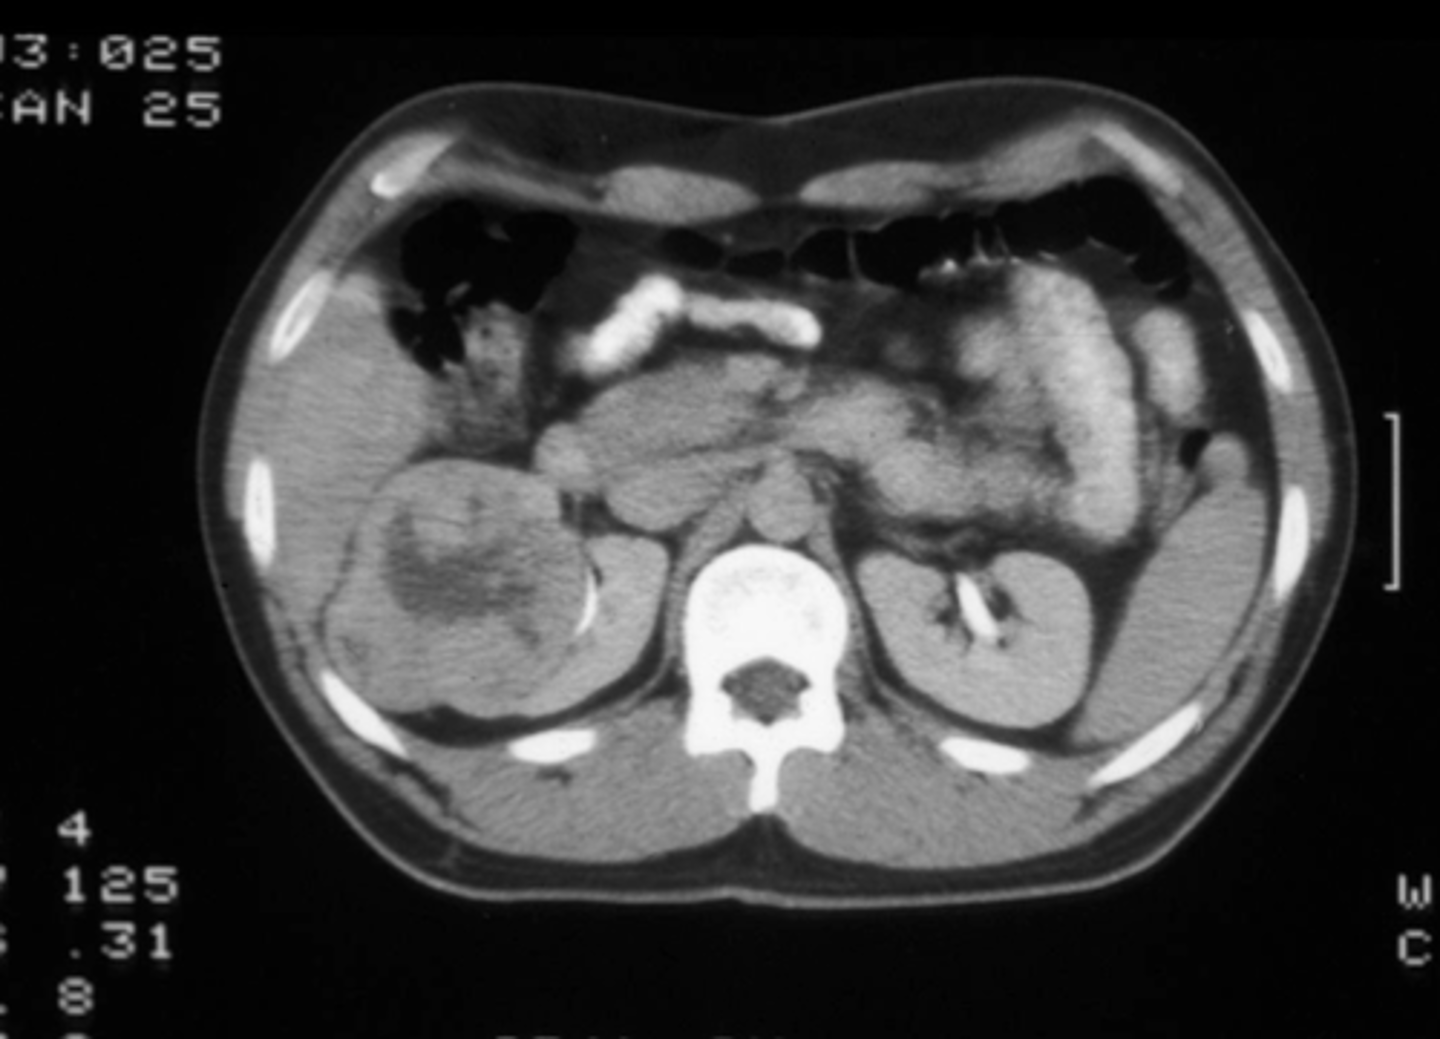

How is RCC diagnosed?

Abdominal CT w/ & w/o contrast plus delayed imaging, urine cytology, renal biopsy required for definitive diagnosis